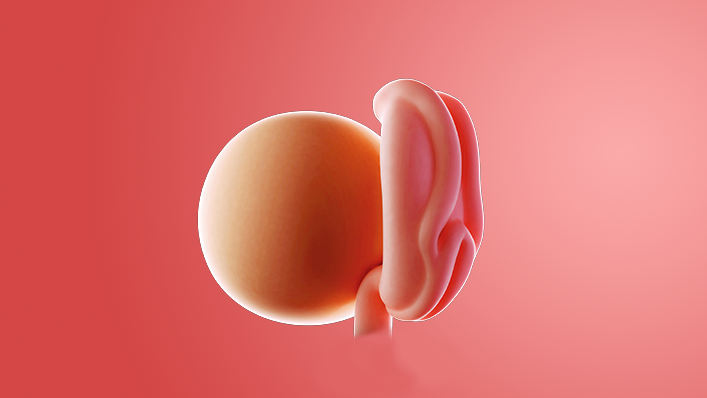

What does my baby look like?

Your baby, or embryo, is around 2mm long (about the size of a sesame seed).

The face is starting to take shape, with a tiny nose and little eyes, which stay closed until around 28 weeks. Your baby's brain and spinal cord are forming rapidly inside you.

Your baby already has some of its own blood vessels and a string of them will make up the umbilical cord. This cord delivers everything it needs from the placenta.

The placenta, which is being created now, will give your baby nutrients and oxygen, while removing waste products.